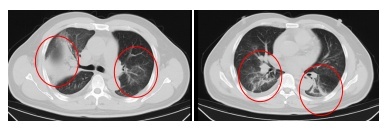

发烧门诊医师详确征询顾先生的既往病史,并为其进行缜密的体格查验。胸部CT后果骄慢,顾先生的双肺存在大面积的炎症病变。

在感染科医护团队的尽心诊疗与缜密防守下,顾先生的发烧、咳嗽、胸闷等症状逐渐缓解。复查的CT后果骄慢,肺部炎症情况赢得了澄莹的改善。现在,顾先生照旧顺利康复出院。